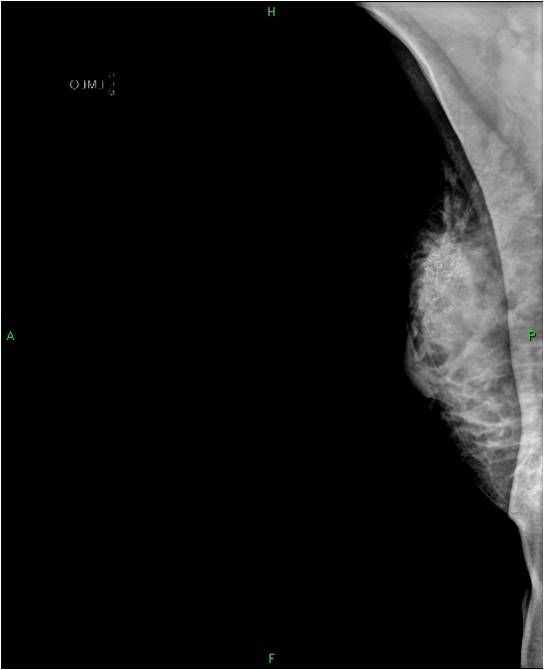

Pathologic lesions in the breast appear as various shapes and densities of soft tissues or calcificications or as the combinations of these two on mammography (Picture 16.). At many times only a few scattered, ill-defined, pleiomorphic microcalcifications indicate the presence of a pathologic lesion.

The soft-tissue lesions can appear as well-defined, rounded or oval shaped (Pictures 13.,14.) or as ill-defined, star-shaped masses (Picture 15.). Rounded or oval lesions are in most cases benign and their malignant proliferation is rare, they do not require surgical removal. These lesions are usually cysts and fibroadenomas, at other times hamartomas, lipomas and at very few times malignant tumors.

Image

Picture 13.

Picture 14.